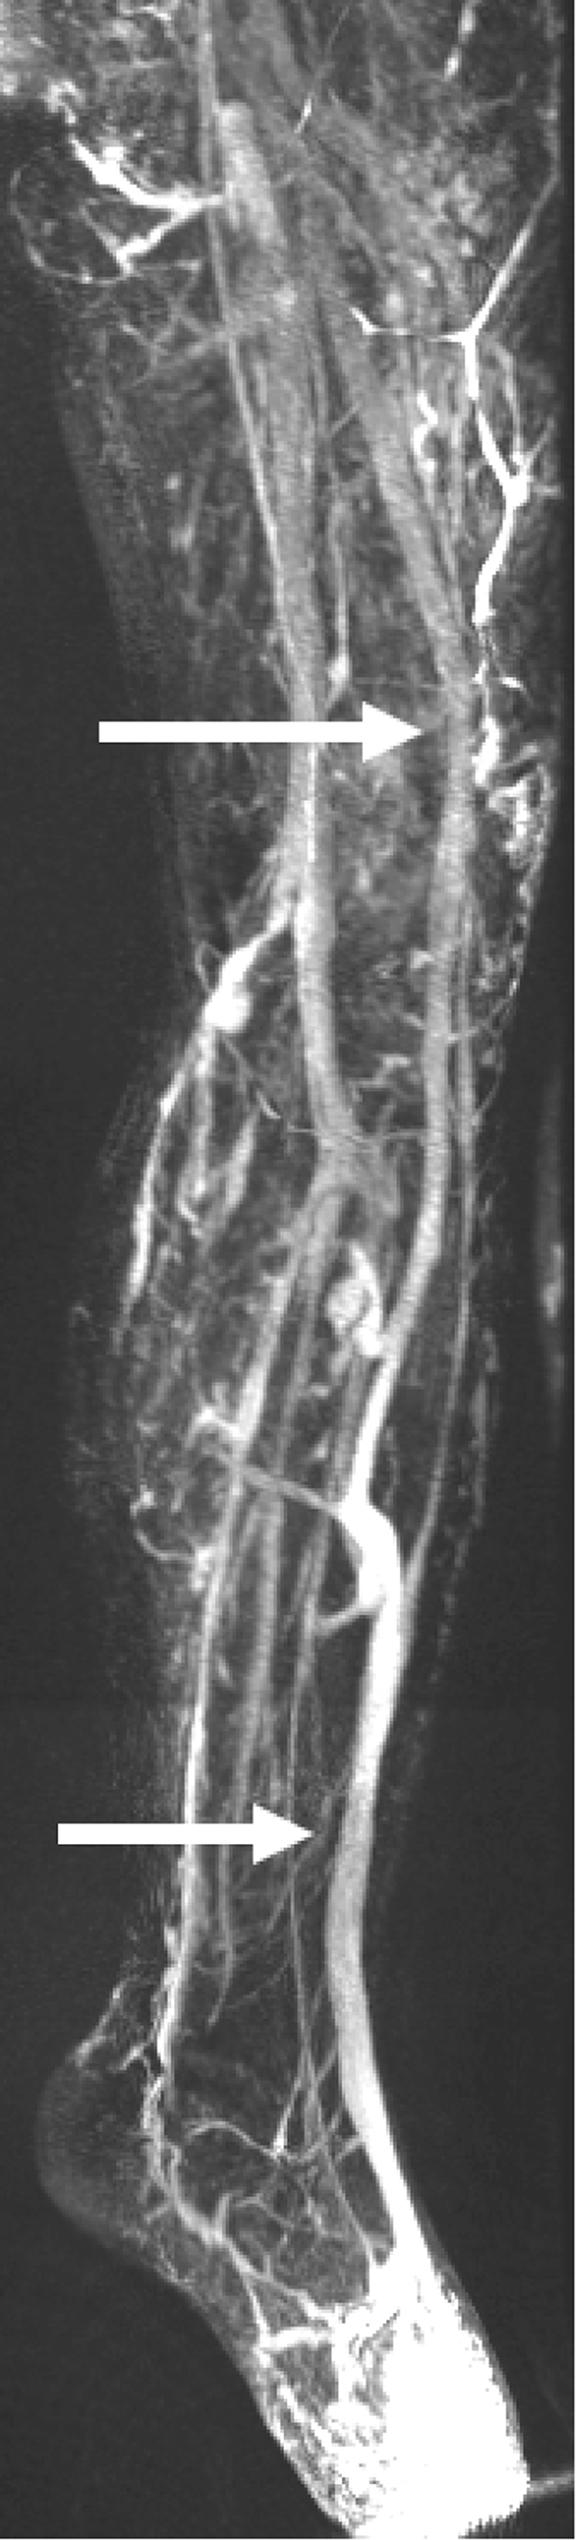

Klippel-Trénaunay syndrome is characterized by a persistent lateral embryonic vein. This so-called marginal vein has a large diameter causing venous stasis and venous hypertension because of the absence of valves along its entire length. The extensive diameter of the vein impedes successful treatment by sclerotherapy. Surgical removal is considered technically challenging for potential severe intraoperative blood loss due to the large perforators to the deep veins. Here we show that endovenous treatments (laser ablation, cyanoacrylate adhesive) might be feasible options in therapy for lateral embryonic veins.

克-特综合征的特征是存在持续的胚胎外侧静脉。这条所谓的边缘静脉直径较大,由于其全长无瓣膜,导致静脉淤滞和静脉高压。静脉直径过大阻碍了硬化疗法的成功治疗。由于通向深静脉的大穿支静脉,手术切除在技术上具有挑战性,可能会导致术中严重失血。在此我们表明,腔内治疗(激光消融、氰基丙烯酸酯粘合剂)可能是治疗胚胎外侧静脉的可行选择。